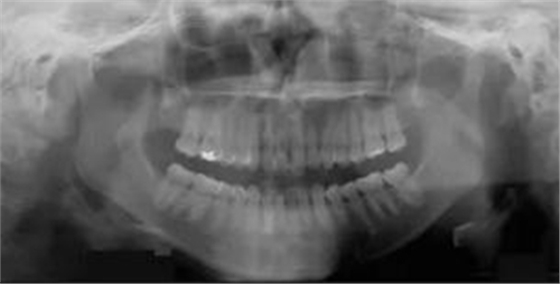

頭側(cè)分析提示為骨性安氏II類(ANB,8.4°;Wits,3.6mm),高角(SN-MP,44.9°),上頜切牙略舌傾(U1-SN,96.2°),下頜切牙略舌傾(IMPA,88。3°)(圖2;表)